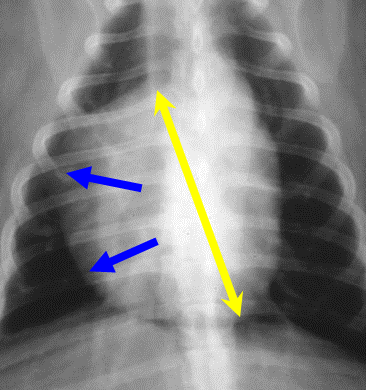

Describe this DV view of LHS enlargement?

DV view

General rounding and sits over the right when it should sit to left.

Line from apex to bifurcation, don’t have 1:1 ration, have a 2:1 ratio